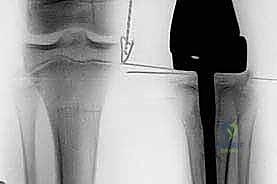

- الأشعة السينية (X-rays): الخطوة الأولى والأساسية. تظهر الأشعة السينية التغيرات في بنية العظم، مثل تدمير العظم أو تكوين عظم جديد بشكل غير طبيعي.

- التصوير بالرنين المغناطيسي (MRI): يوفر صوراً مفصلة للغاية للأنسجة الرخوة المحيطة بالعظم (العضلات، الأوعية الدموية، الأعصاب) ويحدد الامتداد الدقيق للورم داخل نخاع العظم وخارجه، وهو أمر حاسم لتخطيط الجراحة.